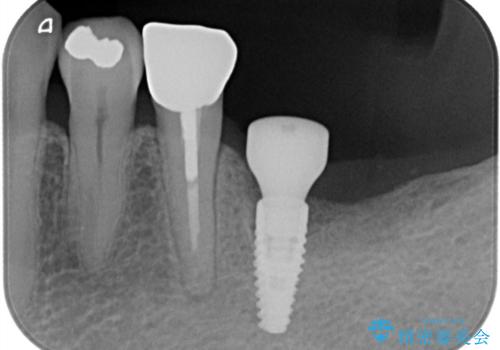

残根状態の歯を抜歯後、抜歯窩の治癒を待ちインプラントを埋入しています。

アバットメントの材質は咬合力を考慮しチタン合金にしました。

被せ物はオールセラミッククラウンを入れています。